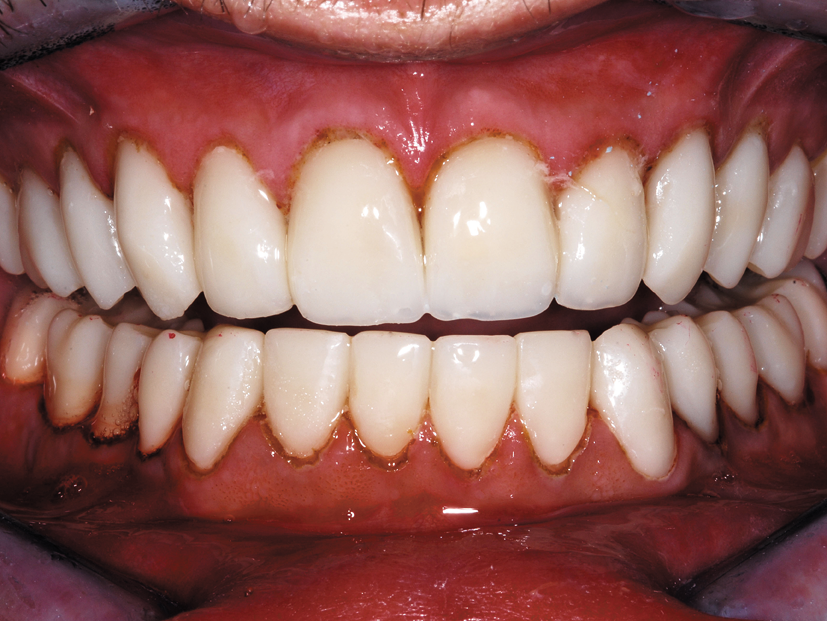

After the build-up material was completely hardened, the anterior teeth were prepared for 360 degree e.max veneers (Fig. 7). The six posterior teeth were prepared for e.max® onlays (Fig. 8). The rubber dam was removed, impressions taken, and Radica temporaries made with Radica, shade B1.

He returned the following morning and the entire lower arch was prepared and impressed in a similar manner (Fig. 9). After completing the lower Radica temps, final bite records were taken in centric relation and all temps were luted with spot bonded flowable resin (Fig. 10).

This case illustrates the ideal use of esthetic core build-ups that need to finish with the look of natural dentin so they blend in with minimally-prepared adjacent teeth. The finished preparations on teeth #7-11 are the same color and shape as the adjacent prepared natural teeth without build-ups.